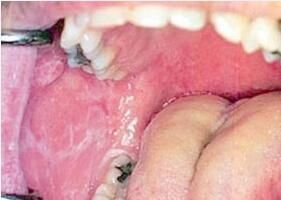

口腔扁平苔藓的糜烂型是常见的一种,范围相当广泛,几乎可遍及整个口腔粘膜。在某些区域尚可隐约显示白纹样损害,没有典型表现,不能临床提供诊断依据。附着龈的糜烂常可见残留的疱壁,状如“上皮剥脱”,这种具有剥脱性的临床表现可见于多种炎症性疾病(天疱疮、类天疱疮等),所以旧称“剥脱性龈炎”,现在不能单凭这个特点判断是不是口腔扁平苔藓了。对于抗生素与*抑制剂治疗常具有对抗性,须进行全面的系统性检查,以免贻误诊与治疗。

口腔粘膜损害,主要特征为珠光白色条纹。白纹可以向各个方面延伸,整个线条不被红纹“切割”,凡白纹稠密时可交织成网状,稀少时可呈树枝状,也可为单线条或绕成环形。类型虽多,但分型并无重要临床意义。损害往往具有明显的左右对称性,粘膜柔软,弹性正常,但有粗糙感,轻度刺激痛。